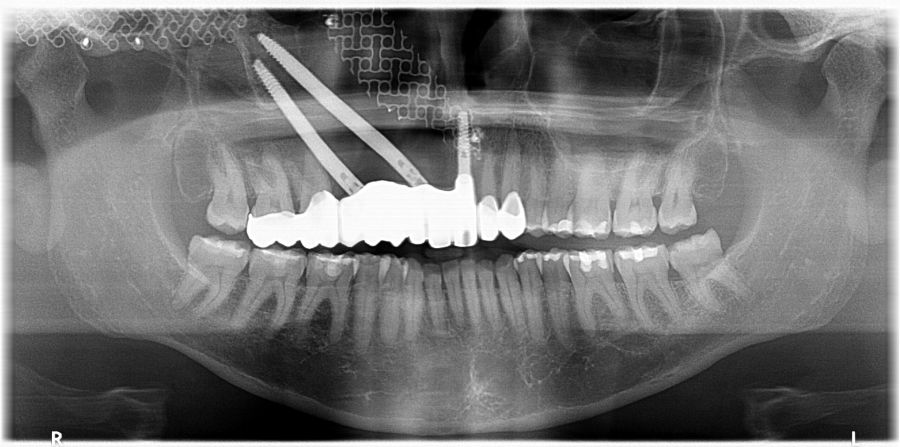

Bajo anestesia general, se realizó la resección quirúrgica junto con la fijación de dos placas preformadas y colocación simultánea de dos implantes cigomáticos y un implante endoóseo en posición del 2.1 (Figuras 5 y 6). Debido a la presencia de márgenes quirúrgicos comprometidos en el informe anatomopatológico, se indicó la administración de radioterapia adyuvante. Por este motivo, se decidió realizar un puente provisional dentosoportado de 1.7 a 2.3 (Figura 7) para mejorar la situación estética y funcional de la paciente durante todo el proceso y evitar un colapso de los tejidos blandos por la radioterapia. Para ello, se tallaron los molares (1.7, 1.6) e incisivo lateral y canino (2.2, 2.3), y se fabricó un puente fresado en polimetilmetacrilato (PMMA) con refuerzo metálico (Figuras 8 y 9).

Una vez finalizada la radioterapia, la paciente se encontraba libre de enfermedad. Por lo que se procedió a la restauración definitiva implantosoportada. Tras la segunda fase, se colocaron dos pilares transepiteliales Multiunit Ò rectos y un pilar Multunit Ò angulado de 17º (Figura 10).

Finalizado el tratamiento oncológico y confirmada la ausencia de enfermedad activa, se procedió a la segunda fase quirúrgica con la colocación de pilares transepiteliales Multiunit®. La integración de los implantes cigomáticos y del implante endoóseo fue satisfactoria, observándose estabilidad clínica y ausencia de signos de periimplantitis.